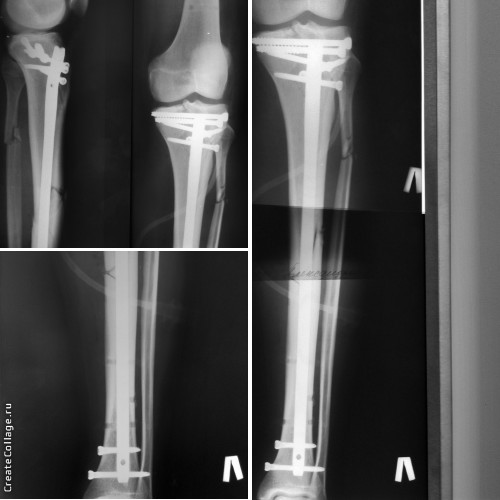

[Ortho] Перелом плато и диафиза большеберцовой кости

Результат